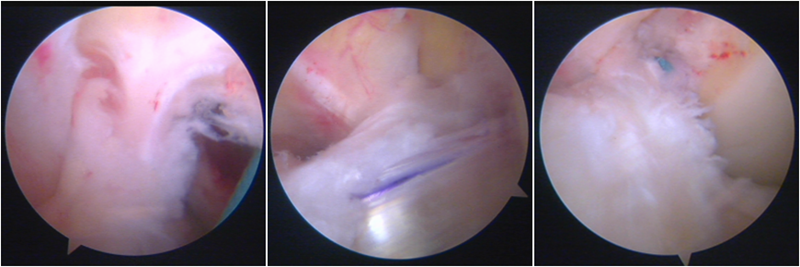

镜下显示ACL残束

内侧半月板

外侧半月板

股骨侧保残骨道建立

股骨侧骨道建立,椭圆形扩孔保残9mm

韧带导入过程

送止血带后韧带表明血管膜